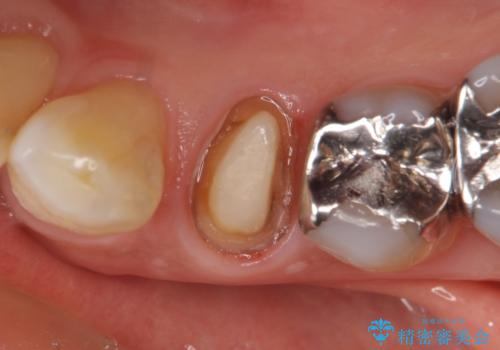

- 他院にて左下4の根管治療を行っていたが、疼くような痛みが引かないため当院にいらっしゃった方の症例です。

左下4の再根管治療を行い症状が治まったのち、オールセラミッククラウンによる補綴を行いました。